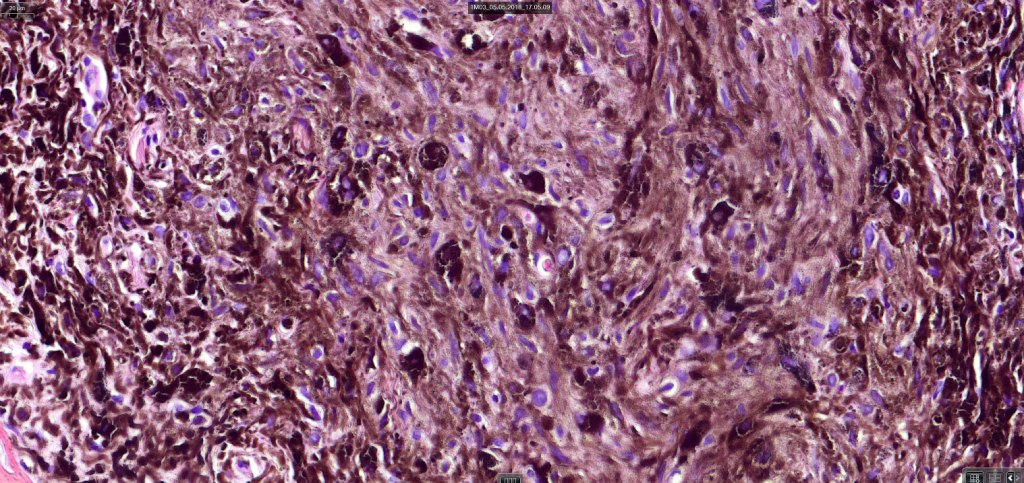

Cellular blue nevus

This uncommon most often devlops on the buttocks, sacrococcygeal region & distal extremities although it may be seen at just about any site. It shows a predilection for females and is diagnosed most often in the 2nd-4th decade. It presents as a blue-black/ or black nodule measuring 1-2 cm in dianeter. Similar to common blue nevus, the cellular variant can be encountered in a wide range of non-cutaneous locations.

Histological features

•Most characteristic is the dumbbell silhouette although a plague morphology may also be encountered

•Admixture of spindle cells, pigmented bipolar or dendritic cells & melanophages

•Cytoplasm is pale and nuclei are small with inconspicuous nucleoli

•An alveolar pattern is characteristic particularly with clear cell nodules

•Mitoses are typically very sparse or absent

•No atypical mitoses

•No Necrosis or lymphovascular invasion

•Multinucleate giant cells sometimes present

•Stromal fibrosis, myxoid change, vascular hyalinization with cyst formation are often seen

•Some tumors are composed spindle cells in a fascicular or neuronevoid pattern